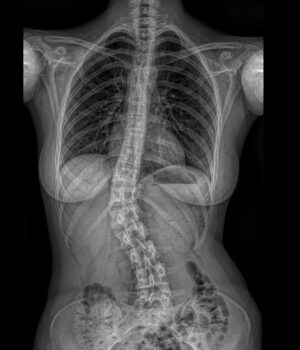

RTG celé páteře (EOS)

Jako první zobrazovací metodu obvykle provádíme RTG, případně EOS. Poskytuje nám obraz páteře v předozadní a boční rovině a umožňuje měřit stupeň zakřivení. RTG provádíme pravidelně na každé kontrole k posouzení vývoje křivky.